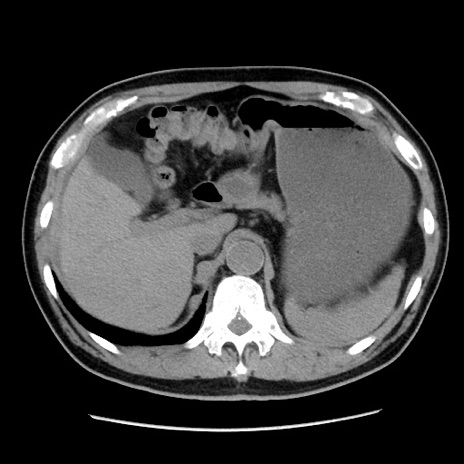

症例16(横断像)

【症例】 70歳代男性

【主訴】 腹痛、嘔吐

【現病歴】 約1ヶ月前より間欠的に腹痛と嘔吐あり、当院消化器内科を受診したところCTで多発する肝臓のLDAを指摘され、精査中であった。以降は消化器症状は安定していたが、2日前より嘔気と腹痛があり、同日より排便・排ガスが消失した。改善認めず、 本日、救急外来を受診した。

【既往歴】 大腸ポリープ切除後。

【身体所見】意識清明・会話良好、BT 36.3℃、BP 127/80mmHg、 P 80bpm、腹部:膨満あり、平坦・軟、上腹部正中および下腹部正中に圧痛あり、反跳痛なし、筋性防御なし。

【データ】WBC 7200、CRP 0.77